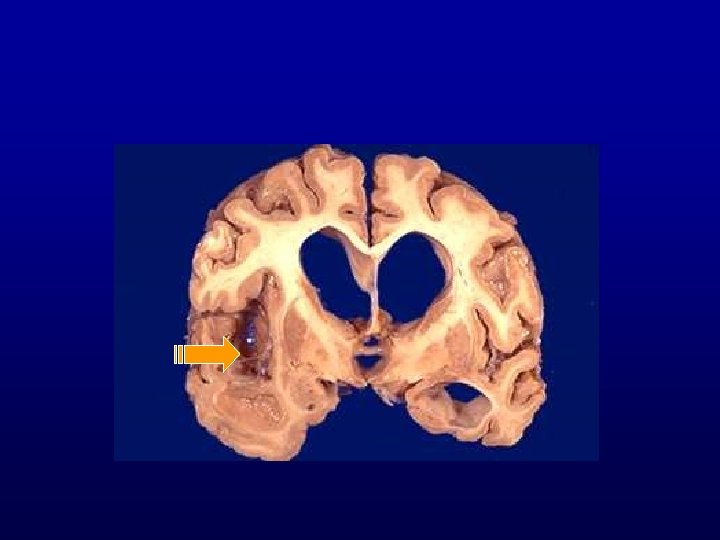

Brain Abscess • Bacterial and fungal organisms • Sources of brain abscesses – Otogenous (temporal lobe or cerebellar) – Rhinogenic (paranasal sinuses) – Traumatic (e. g. , stab wound) – Metastatic, hematogenously spread from • Bacterial endocarditis, septicemia • Lung abscess or bronchiectasis • Intestinal flora in congenital heart disease with a right to left shunt • Osteomyelitis

Pathogenesis of brain abscess • Preexisting necrosis: – Direct extension from adjacent focus (thrombophlebitis venous infarct) – Infected emboli (occlusion of a small artery or arteriole arterial infarct) • Necrosis leads to frank suppuration • After a week or two, a fibrous wall (derived from the vasculature) that may be several mm thick after 4 -5 weeks forms • Outside the fibrous wall, there are perivascular, chronic inflammatory cells and white matter edema (perifocal edema) • An intense astrocytic gliosis takes place with formation of a glial scar

• Location • Mastoiditis temporal lobe or cerebellar abscess • Frontal sinusitis and ethmoiditis frontal lobe abscess • Metastatic (hematogenously derived) abscesses anywhere Disseminated (metastatic) microabscesses are usually due to sepsis or acute bacterial endocarditis, and are multiple • Common organisms are Staph, Candida, and anaerobes (Bacterioides Fragilis) • Patients always have underlying immunosuppression

Complications of brain abscesses • Destruction of vital centers (e. g. , medulla oblongata) • Rupture of the abscess causes empyema: – Meninges (leptomeningitis) – Ventricles (ventriculitis) • Increased intracranial pressure, due to: – Mass effect from large abscess – Perifocal inflammatory edema

Pathogenesis&Complications Necrosis Supuration Fibrous wall Empyema Gliosis Perifocal edema Mass effect Intracranial pressure

BRAIN ABSCESS